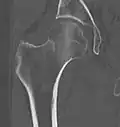

X-ray showing a suspected compressive subcapital fracture as a radiodense line -